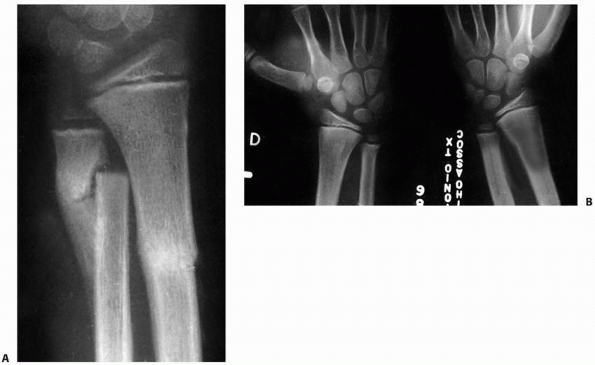

FIGURE 9-16 A. AP and lateral radiographs of severely displaced Salter-Harris type II fracture of the distal radius. B. Closed reduction shows marked improvement but not anatomic reduction. The cast had to be bivalved due to excessive swelling. (continues)

FIGURE 9-16 (continued) C. Unfortunately, the patient lost reduction after a new fiberglass cast was applied. D. Out-of cast-radiographs show a healed malunion in a similar position to the prereduction radiographs.